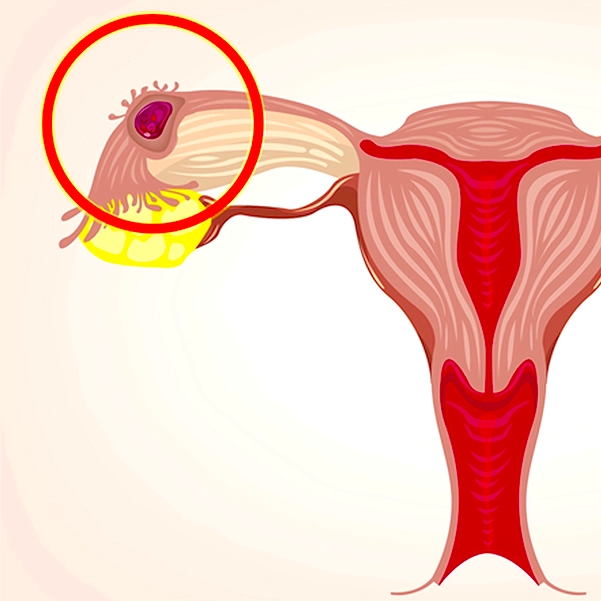

حاملگی خارج رحم (Ectopic Pregnancy) زمانی رخ میدهد که تخمک بارور شده به جای قرار گرفتن در داخل رحم، در جای دیگری مانند لولههای فالوپ، تخمدان یا حتی شکم کاشته شود. این وضعیت میتواند بسیار خطرناک باشد و نیازمند توجه فوری پزشکی است. علاوه بر اهمیت رعایت نکات مربوط به تغذیه در دوران بارداری برای سلامت جنین، در این شرایط توجه ویژه به علائم حاملگی خارج رحم ضروری است. در ادامه به مهمترین علائم این بیماری اشاره میکنیم:

بارداری خارج رحم زمانی رخ میدهد که تخمک بارور شده به جای رحم، در جایی دیگر مانند لولههای فالوپ، شکم یا دهانه رحم کاشته شود. این وضعیت معمولاً به دلیل مشکلاتی در عبور تخمک از لولههای فالوپ به رحم ایجاد میشود. عواملی مانند التهاب یا عفونتهای مزمن لگنی، آسیبهای قبلی به لولهها، جراحیهای ناحیه شکم یا لگن، استفاده از روشهای پیشگیری از بارداری داخل رحمی (IUD) و حتی سابقه حاملگی خارج رحم قبلی میتوانند احتمال بروز این نوع بارداری را افزایش دهند. به همین دلیل، شناخت عوامل خطر و پیگیری به موقع توسط پزشکانی مانند خانم دکتر نسیم سرمست بسیار حیاتی است تا از بروز عوارض جدی جلوگیری شود.

انواع بارداری خارج از رحم

بارداری خارج از رحم میتواند در چندین ناحیه از بدن اتفاق بیفتد که انواع مختلفی دارد.

- بارداری لولهای (Tubal Pregnancy):

رایجترین نوع بارداری خارج از رحم است که در لولههای فالوپ اتفاق میافتد. در این حالت تخمک بارورشده در لوله فالوپ لانهگزینی میکند و شروع به رشد میکند، که میتواند باعث پارگی لوله و خونریزی شدید شود. - بارداری تخمدانی (Ovarian Pregnancy):

در این نوع، تخمک بارورشده در تخمدان جایگزین میشود. این نوع بارداری بسیار نادر است و تشخیص آن معمولاً دشوارتر از نوع لولهای است. - بارداری دهانه رحمی (Cervical Pregnancy):

در این حالت، تخمک بارورشده در دهانه رحم قرار میگیرد. این نوع بارداری نیز نادر بوده و میتواند باعث خونریزی شدید شود. - بارداری شکمی (Abdominal Pregnancy):

تخمک بارورشده در حفره شکمی لانهگزینی میکند. این نوع نیز بسیار نادر است و به دلیل محل غیرمعمول، خطرات و پیچیدگیهای بیشتری دارد. - بارداری در ناحیه رحم (Interstitial or Cornual Pregnancy):

در این نوع، تخمک در بخشی از لوله فالوپ که به داخل رحم وارد میشود (بخشی که داخل عضله رحم است) لانهگزینی میکند. این نوع میتواند منجر به خونریزی شدید و مشکلات جدی شود.